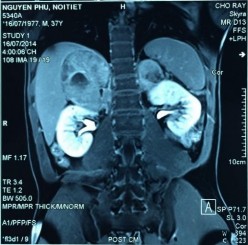

Phim MRI bướu tuyến thượng thận 2 bên

Bệnh phẩm bướu sắc bào tủy TTT bên trái

Phim MRI sau phẫu thuật cắt bướu TTT bên trái

[Nguyễn P., 37 tuổi, SNV: 214061952]